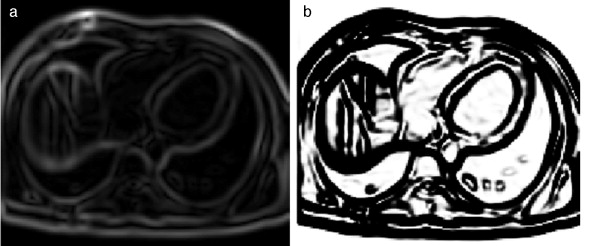

En la figura 28 se presentan los resultados obtenidos al aplicar las rutinas mencionadas. En la figura 28 .a se presenta el corte 98 de la imagen de phantom original. En la figura 28 .b se presenta un corte de la imagen de phantom corrompida con ruido gaussiano . En la figura 28 .c se presenta la imagen filtrada con difusión anisotrópica. En la figura 28 .d se presenta la segmentación obtenida empleando la rutina Watershed . En la figura 28 .e se presenta la zona de la materia blanca proporciona por BrainWeb .

|

|

|